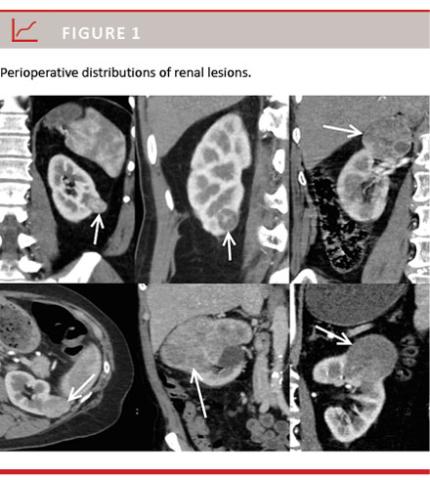

A total of 226 patients underwent PN or RN, and 75 patients were excluded from the study: 25 patients with cystic lesions, 16 patients who had undergone kidney biopsy prior to surgery, 14 patients who had locally advanced lesions and 20 patients with metastatic disease. A total of 151 patients were included in the study. In these patients, CT revealed suspected renal lesions and patients underwent RN or PN. The distribution of lesions is shown in Figure 1. The mean age was 62.9 years (range: 37-86 years) with a male:female ratio of 3:1. The median tumour size was 4.2 cm (range: 1.1-22 cm). The median SL size was 2.5 cm (range: 1.1-4.0 cm), median IL size was 5.5 cm (range: 4.2-7.0 cm) and the median LL size was 11.0 (range: 7.5-22 cm). PN was performed in 69.3% of SL patients versus 23.4% of IL patients (p < 0.001). All LL patients underwent RN. The distribution of benign lesions was not significant in all cohorts (p = 0.27).